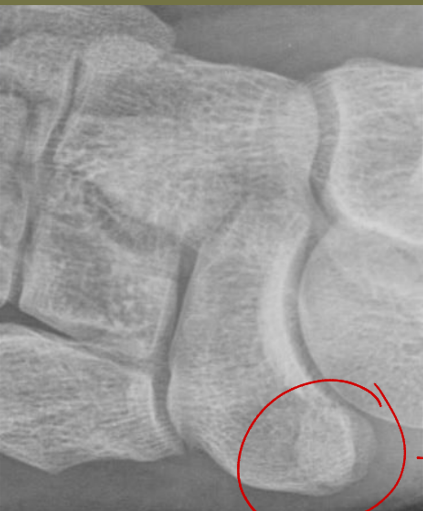

Cartilage Space: What are the components you are examining?

• Joint space (normal width/symmetry)

• ↓ joint spaces, osteophytes + sclerosis, loss of smooth joint surface (contour)

• Subchondral bone (Smooth surface - no irregularity)

• ↑ sclerosis and erosion

• Epiphyseal plates (normal thickness/position relative to secondary epiphysis)

• Abnormal thickness, irregular margin